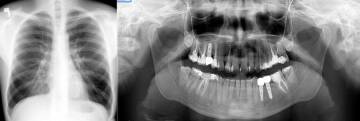

Nowoczesne kliniki stomatologiczne, zwłaszcza te w Łodzi, korzystają z najnowocześniejszych technologii radiologicznych, aby zapewnić dokładne diagnozy. RTG panoramiczne zębów jest podstawowym narzędziem, które pozwala ocenić nie tylko korony, ale również korzenie zębów ukryte pod dziąsłami oraz stan kości. Wysokiej jakości aparaty RTG minimalizują ryzyko dla pacjenta, dostarczając jednocześnie cennych informacji o stanie zdrowia zębów i kości szczęki.

- Badanie radiologiczne: W tym zdjęcia RTG, zarówno pantomograficzne jak i tomograficzne (RTG 3D), które ujawniają szczegóły niewidoczne podczas standardowego badania.

Dzięki nowoczesnej diagnostyce radiologicznej możliwe jest uzyskanie kompleksowego obrazu stanu zdrowia jamy ustnej, co jest nieosiągalne przy metodach tradycyjnych. Wczesne wykrycie problemów, takich jak niebezpieczne zmiany w okolicy wierzchołka korzenia, pozwala na podjęcie szybkich działań, które mogą uratować zdrowie i estetykę uśmiechu pacjenta.

W przypadku nowoczesnej aparatury cyfrowej korzyści zawsze wygrywają. Dawka promieniowania jest najniższe z możliwych, a wczesne wykrycie toczącego się poddziąsłowo procesu chorobowego pozwoli uniknąć poważnych konsekwencji! W praktyce pozornie zdrowe uzębienie często ujawnia niebezpieczne zmiany w okolicy wierzchołka korzenia zębowego! Niestety alarmujące objawy najczęściej pojawiają się zbyt późno! Oprócz utraty zdrowia narażamy się na rosnące koszty leczenia. Najgorszym z możliwych scenariuszy jest sytuacja, kiedy proces chorobowy zniszczył kość w stopniu uniemożliwiającym podjęcie leczenia kanałowego, protetycznego, implantologicznego lub nawet zagrażającym pęknięciem kości żuchwy w wyniku osłabienia kości przez np. rosnącą torbiel.